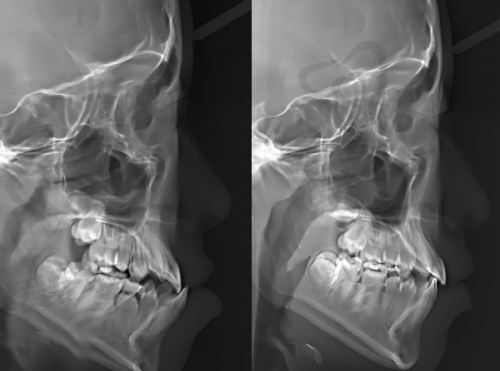

中山贝壳口腔医院在诊疗设备方面投入巨大,引进了大量精良的医疗设备。这些设备能够为医生的诊断和治疗提供正确的数据和清晰的图像,提高治疗的精细度和成功几率。例如,在种植牙手术中,精良的口腔CT设备可以清晰地显示患者口腔内部的骨骼结构和神经分布,帮助医生制定更合理的种植方案。在牙齿正畸方面,数字化正畸设备能够模拟牙齿移动的过程,让患者提前看到治疗成效。